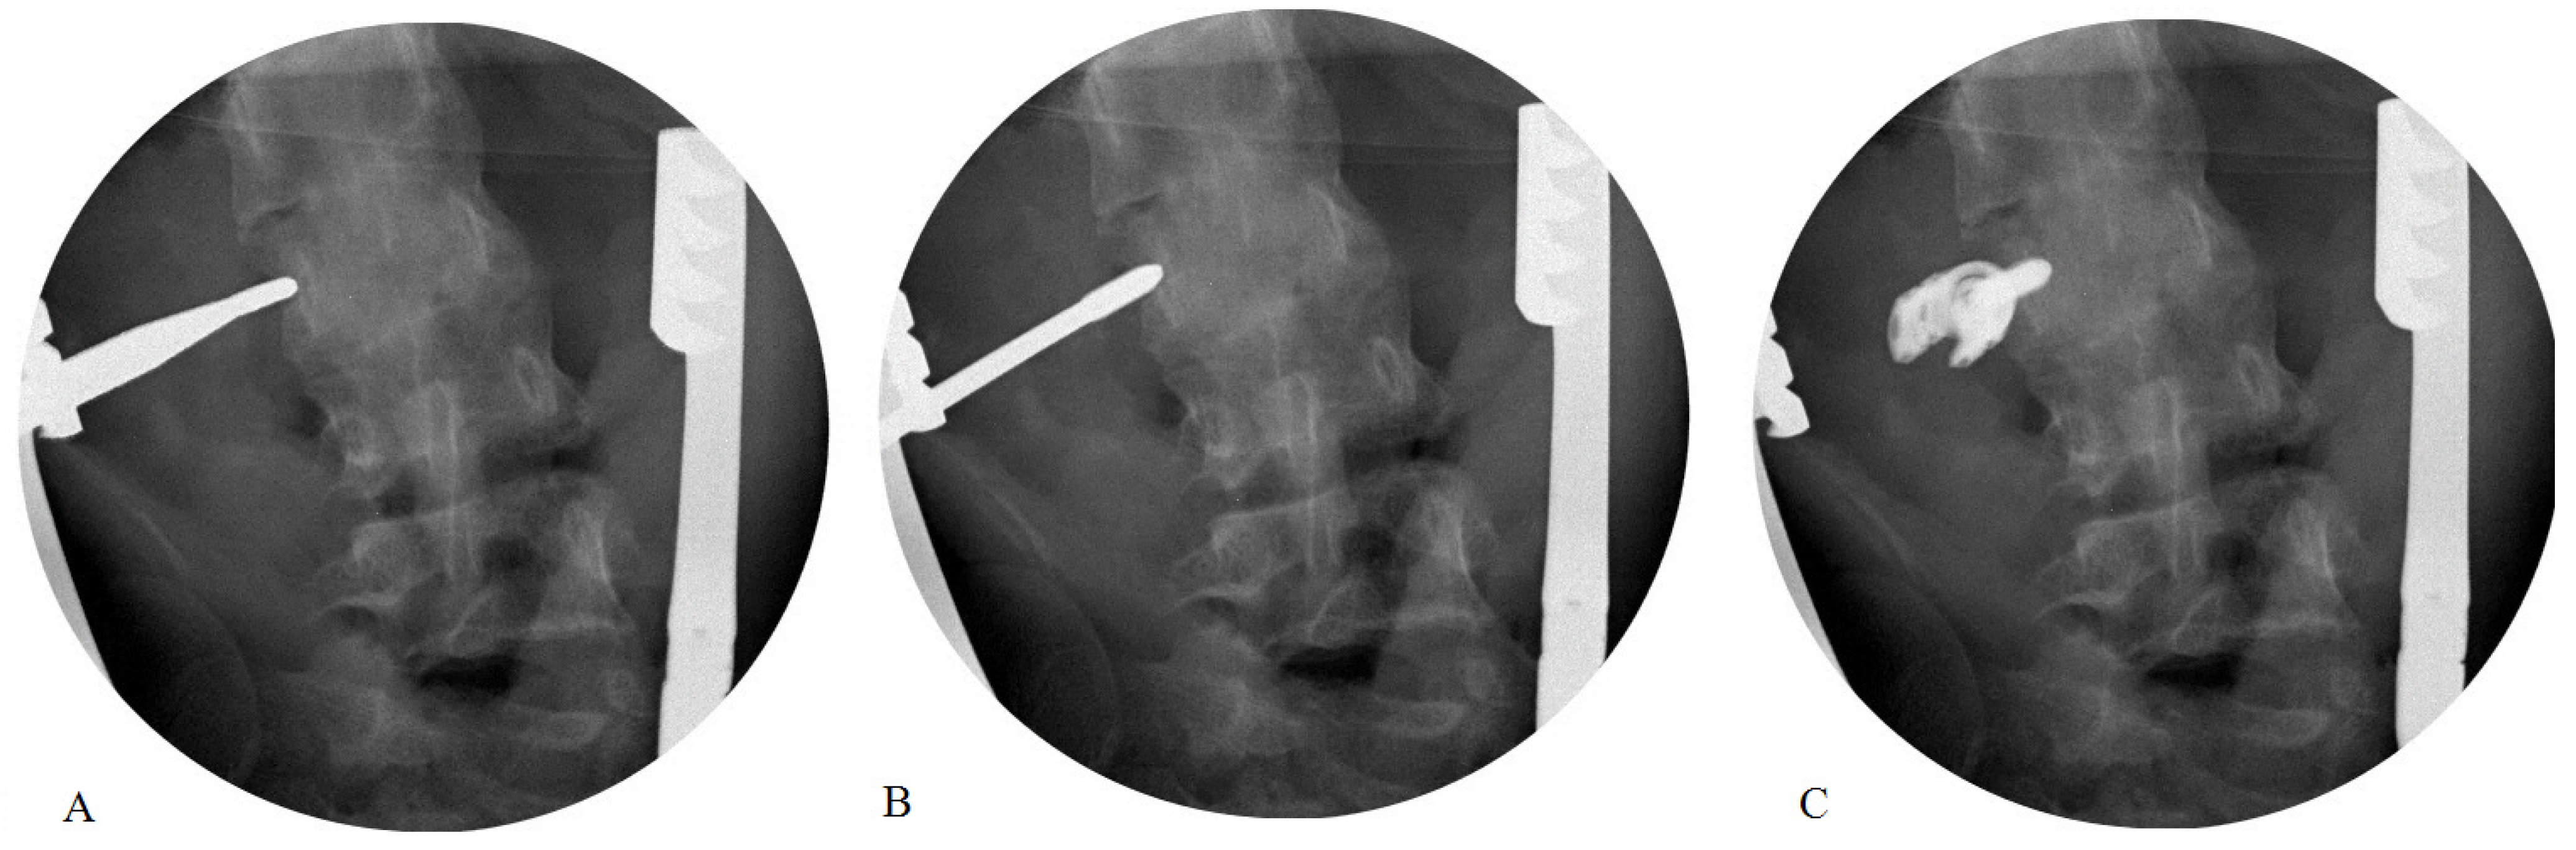

2.3. Surgical Technique